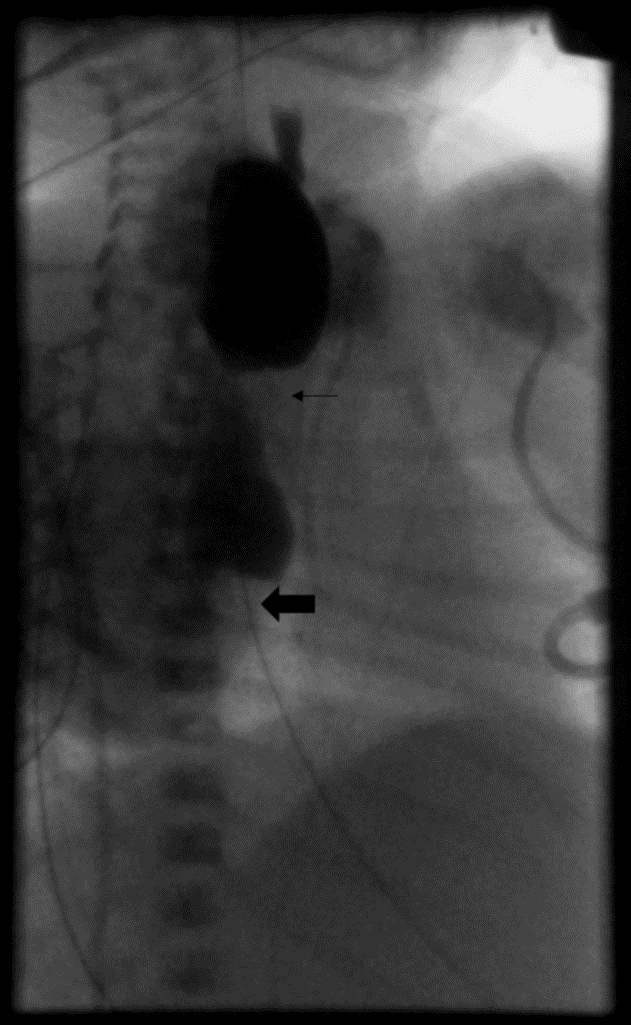

An esophagram was performed on DOL 8 to further evaluate the esophageal anastomosis and distal esophagus. The proximal esophagus was found to be dilated with passage of contrast through the esophageal anastomosis to a 2cm transition point in the distal esophagus with only slow passage of contrast into the stomach (Figure 3). There was no anastomotic leak. By DOL 10 she was tolerating full feeds by NGT and was discharged to an affiliate sub-acute pediatric care facility to allow for healing and weight gain prior to elective repair of the esophageal stricture.

Figure 3. Esophagram performed under fluoroscopy shows narrowing at the esophageal anastomosis (small arrow), with a second area of distal stricture (big arrow) with proximal distension. There was very slow passage of a small amount of contrast into the stomach.